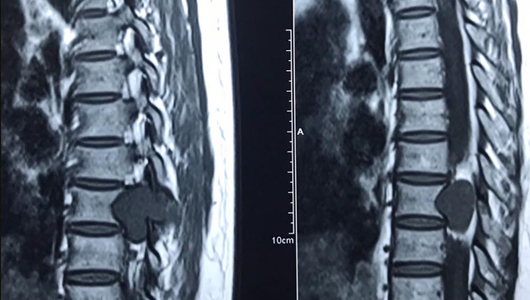

4. Cận lâm sàng chèn ép tủy sống.

4.5. Cộng hưởng từ hạt nhân: